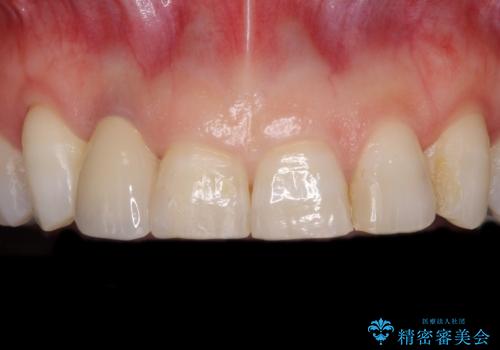

歯肉が腫れている前歯 外科処置を併用したオールセラミッククラウン

- 前歯のクラウン周りに歯肉が腫れていることを気にして来院された患者様です。

元々磨き残しによる歯肉の腫脹がありましたが、クラウンが歯肉深くに装着されていたため、特に腫脹が目立っていました。

仮歯に置き換えた際に歯周外科処置を行い、歯肉の腫脹が落ち着いたことを確認してオールセラミッククラウンにて補綴することとしました。

気になっていた腫脹がなくなり、患者様には大変満足していただきました。